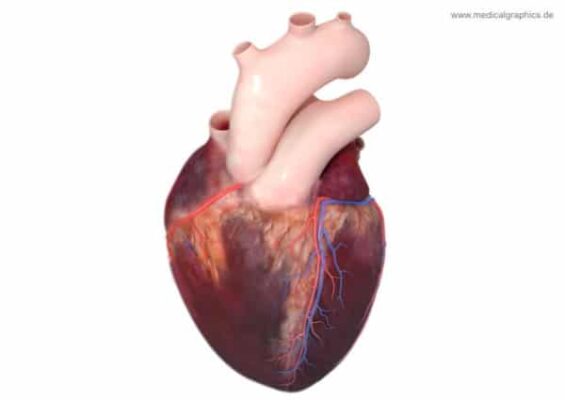

توصلت دراسة علمية إلى أن ‘دغدغة’ الأذن بتيار كهربائي ضعيف قد يساهم في إعادة التوازن للجهاز العصبي اللاإرادي لدى من تجاوزوا 55 عامًا من العمر ، مما قد يؤدي إلى إبطاء أحد آثار الشيخوخة. قام العلماء خلال هذه الدراسة المثيرة بتقديم جلسات علاج يومي قصيرة لمدة اسبوعين بإستخدام تيار كهربي صغير و غير مؤلم للأذن […]